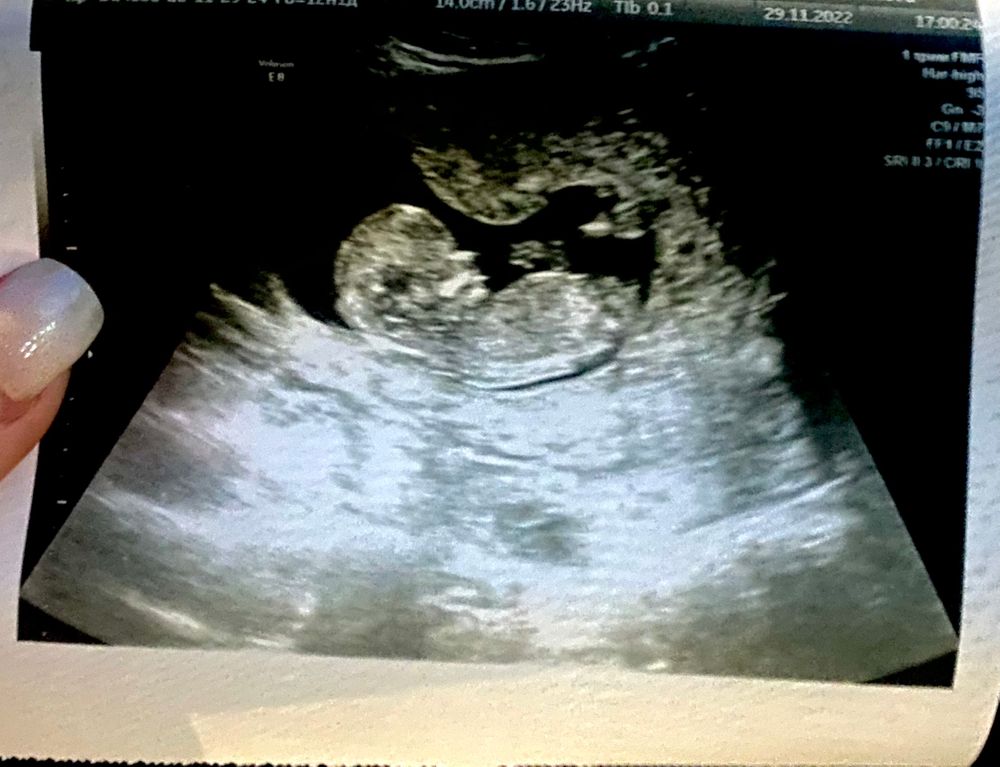

Мы узнали пол 💟

В общем у нас девочка🌸

срок 12+5.

ктр 62 мм

❤️ 160 ударов

На узи дрыгалась как энерджайзер. Вся искрутилась, врач устала ее ловить.